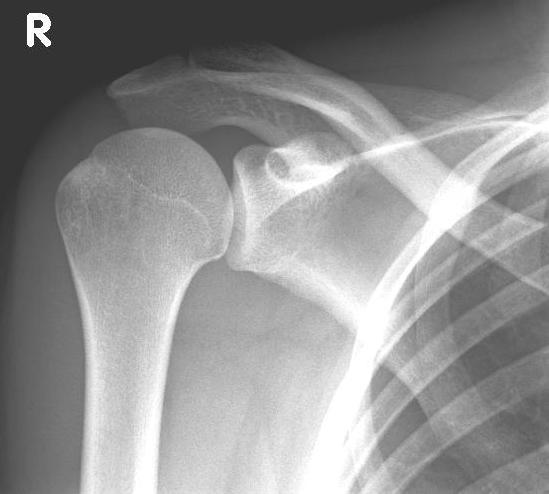

right: X-ray of a healthy shoulder joint

left: X-ray image of an omarthrosis